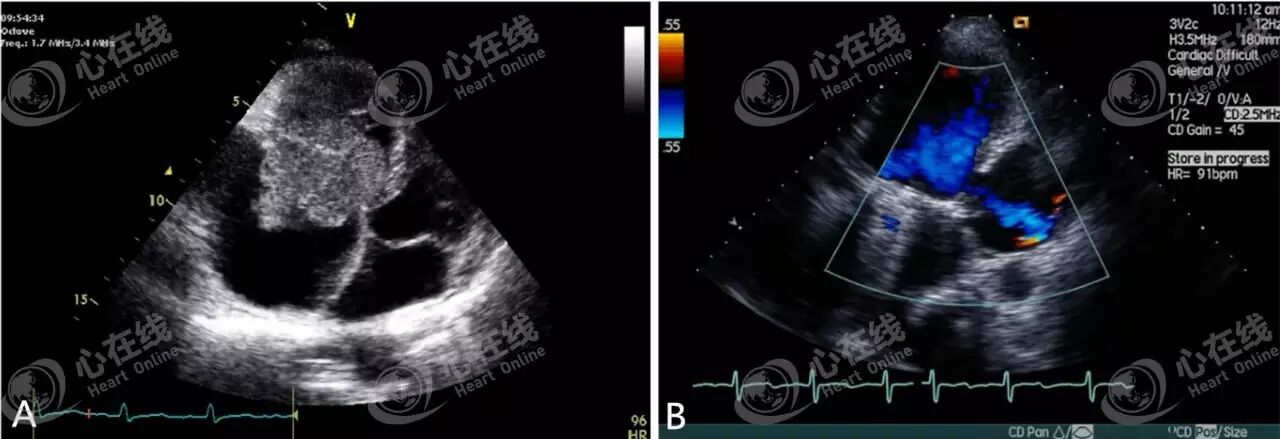

图A显示肌接近断裂,彩色多普勒超声心动图(图B)提示二尖瓣重度关闭不全。